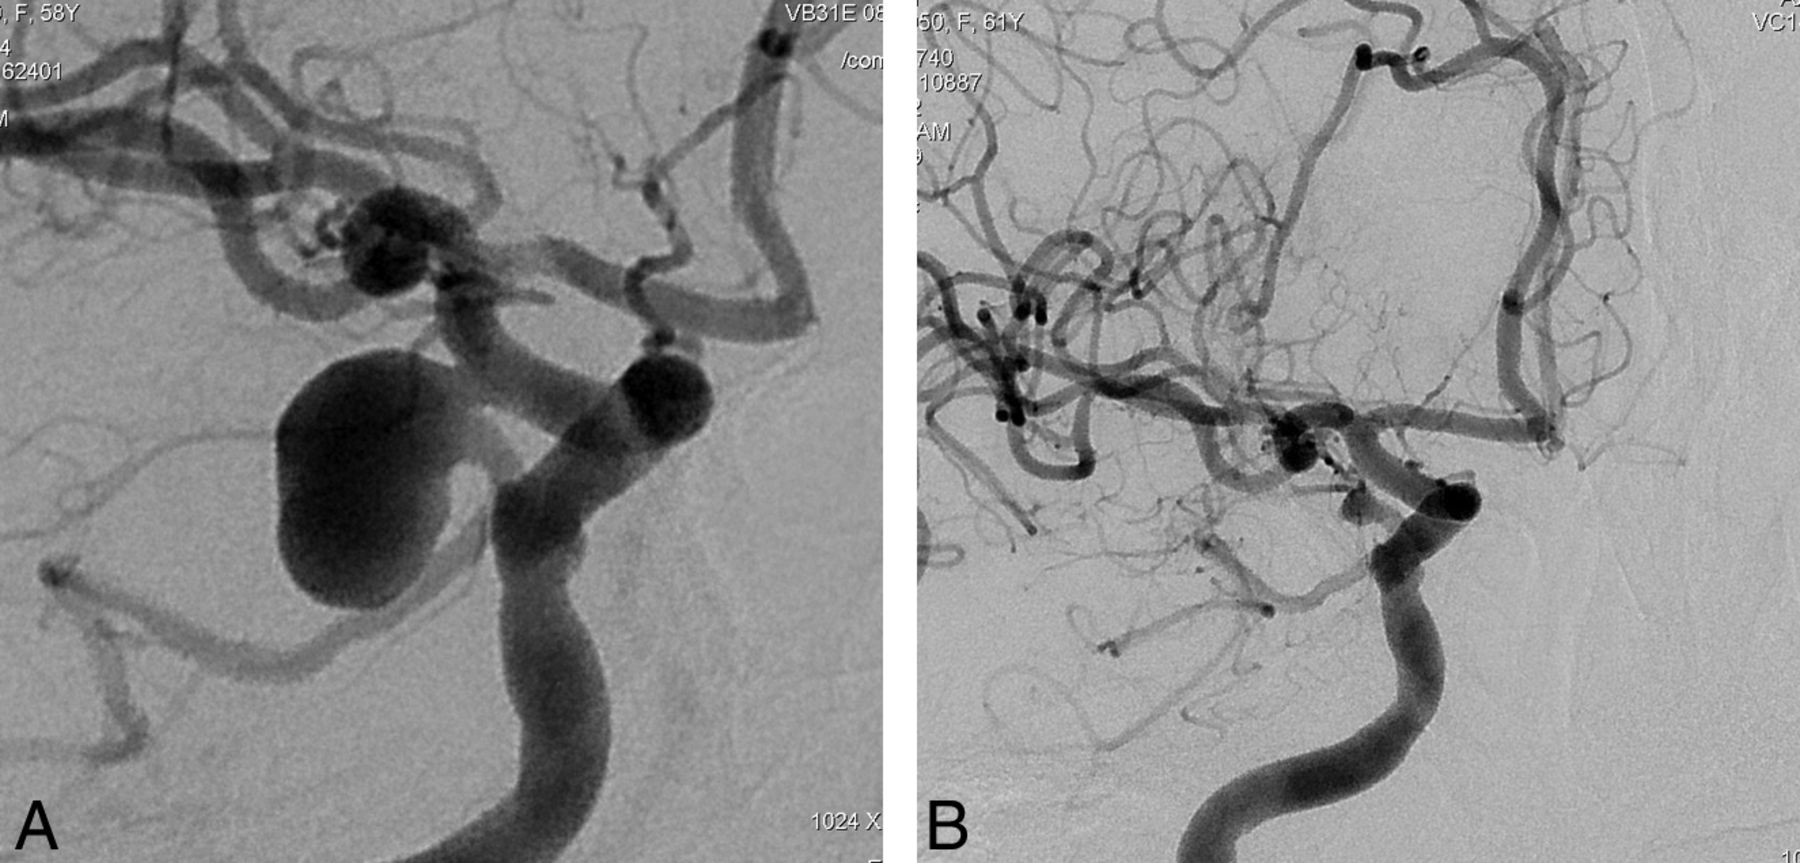

This retrospective study included 251 aneurysms treated with PEDs in 191 consecutive patients (mean age, 49.2 years; age range, 26–71 years; except for 1 pediatric patient who was 13 years of age) between November 2008 and September 2011. One hundred twenty-nine patients were female and 62 were male. Following ethics committee approval, 17 of the patients were included in the Pipeline for Uncoilable or Failed Aneurysms Study. Written informed consent was obtained from each patient. Sidewall aneurysms with wide necks (≥4 mm) or unfavorable dome-neck ratios (≤1.5) (Fig 1), large or giant aneurysms that might have or already had mass effect (Fig 2), fusiform aneurysms (Fig 3), blisterlike aneurysms (Fig 4), recurrent sidewall aneurysms, dissecting aneurysms (Fig 2), aneurysms at difficult angles to the parent artery (so that catheterization of the aneurysm and coiling may have increased risk) (Fig 5), and aneurysms in which a branch was originating directly from the sac (therefore endosaccular obliteration or clipping was likely to compromise the branch or result in a neck remnant) were treated with the PED (Figs 6 and 7). We intended to treat 1 patient with a giant, very wide-neck, cavernous ICA aneurysm presenting with mass effect symptoms by using a PED; however, we failed to bypass the neck of the aneurysm, resulting in treatment of the aneurysm with parent artery occlusion following a balloon occlusion test, without complications. This patient was not included in the study because a PED was not used. This was the only technical failure during the course of the series.

Twenty-eight patients presented with a vision abnormality attributed to mass effect (Fig 2). Three patients worsened immediately following treatment. Two of these 3 regressed to their preoperative presentations during follow-up; therefore, 2 patients did not receive any benefit from treatment. The remaining patient had permanent additional morbidity. The aneurysms of these 3 patients were completely occluded in the control angiographies. Seventeen patients had total recovery of symptoms, and an additional 8 patients improved during follow-up, though the symptoms did not resolve completely.

This series included 46 aneurysms (Figs 6 and 7) in which a branch originated directly from the sac where endosaccular coiling or clipping at the neck would result in incomplete occlusion and/or compromise of the branch. Fusiform aneurysms, which involved perforating branches such as aneurysms of the basilar artery, distal vertebral artery, and the M1 segment of the middle cerebral artery, were not included in this group. This group is the subject of another study and will be analyzed there in detail. However, this group of aneurysms prompted us to find a new definition (ie, “remodeled artery”), which refers to an “infundibulum-like” appearance or a tortuous course of the branch resulting from the significant shrinkage of the aneurysm due to flow change (Fig 7). Sectional imaging confirmed the resolution of the sac in these patients with such large/giant aneurysms. In this subgroup of aneurysms, 42 of 46 aneurysms had at least 1 control angiography at 6 months. Among these 42 aneurysms, 8 showed a so-called “remodelling” pattern (Fig 7).

More important, the PED is providing a solution for aneurysms that have a branch incorporated into the sac. These aneurysms are generally considered “uncoilable” in the endovascular approach, though there have been a few publications reporting the contrary.45,46 On the other hand, in such aneurysms, the flow through the flow diverters is maintained into the branch originating from the sac while occlusion of the aneurysm is still possible. Our series included 46 aneurysms in which a branch was originating from the sac. In none of these aneurysms was the relevant branch occluded, except for 5 PcomA aneurysms in which the PcomAs were occluded, with the ipsilateral PCA filling from the posterior circulation. On the basis of our experience in this group, we observed that the branch originating from the aneurysm sac, which is treated with a flow diverter, is kept patent when there is a flow demand through it. However, only 1 device was placed to cover the sac and the originating branch in this particular subgroup of our series. Therefore, the possible consequences of multiple-device coverage are indeterminate. Regarding this subgroup, we noted a particular appearance in some aneurysms, in which the aneurysm shrunk significantly, resulting in an “infundibula like” appearance at its origin or a tortuous takeoff from the parent artery in place of the initial aneurysm. For the purpose of definition, these are referred to as “remodeled aneurysms.” The detailed results of this subgroup of aneurysms are the subject of another article.